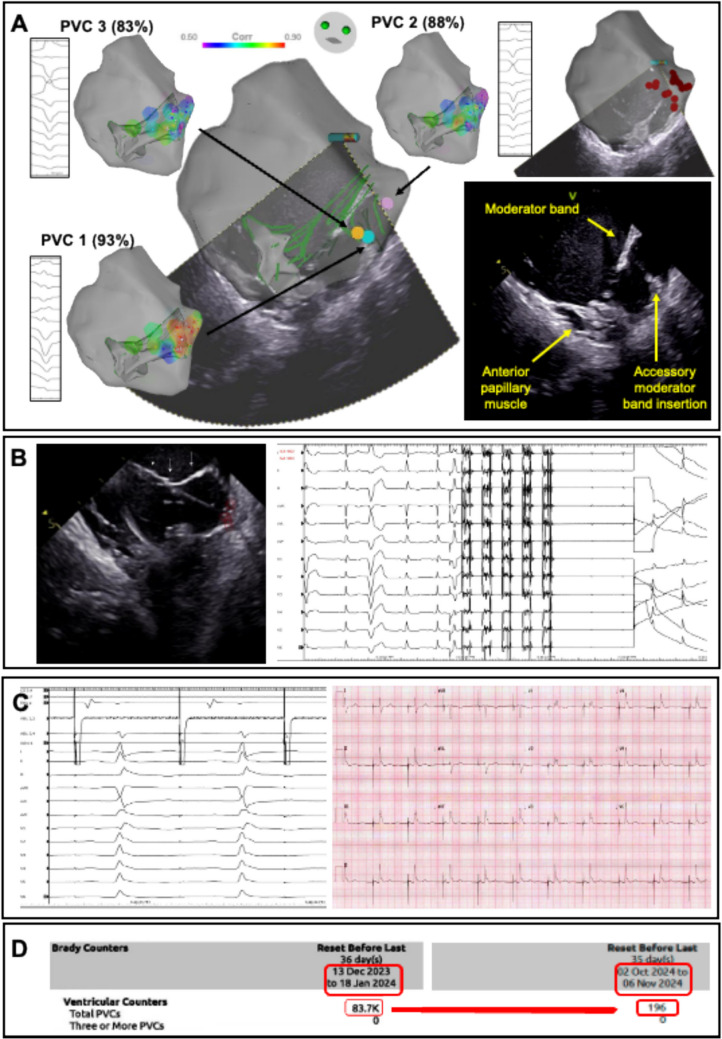

Introduction: Premature ventricular complexes (PVCs) from intracavitary structures, such as papillary muscles and the moderator band, can be challenging to treat. Pulsed field ablation (PFA) offers a novel strategy for treating these arrhythmias.

Methods: Between 2023 and 2024, three patients with intracavitary PVCs (two with PVC-mediated ventricular fibrillation) underwent PFA at a tertiary referral centre. Electroanatomic mapping was performed and, with intracardiac echocardiography (ICE) guidance, PFA was delivered using a pentaspline Farapulse catheter, with adjuvant radiofrequency (RF) ablation as needed.

Results: All patients had successful abolition of PVCs. PFA delivery was feasible and safe, with excellent success despite prior RF ablation failures though one patient required adjuvant RF ablation. The only complication was a persistent right bundle branch block (RBBB) after PFA delivery to the moderator band. Follow-up showed significant reductions in PVC burden and no further ventricular fibrillation (VF) episodes. The mean procedural duration was 153.67 ± 31.71 min, and the mean fluoroscopy time was 14.38 ± 6.74 min.